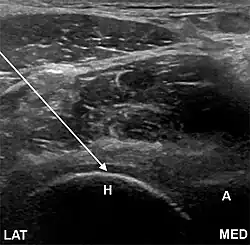

- The anterolateral approach, with the ultrasound probe oriented axially and the femoral head and acetabular rim in view. This often shortens the distance from needle skin entry to joint compared to the longitudinal approach making it a useful approach in larger patients. The introduced needle remains lateral to the femoral neurovascular bundle, and the needle is advanced until its tip rests on the femoral head.